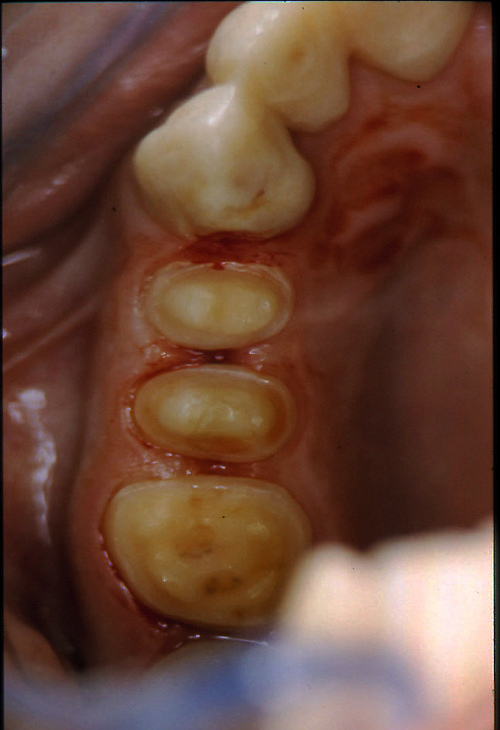

ABSTRACT El Bruxismo es una entidad patológica en la que concurren diferentes factores. Entre ellos el stress que conlleva consigo la vida moderna, constituye el Factor Predisponente sobre el que se ha abundado en innumerables tratamientos de tipo general, actuando sobre la psiquis y el comportamiento del individuo, ya sea con fármacos o bien mediante medios psicológicos. Sin embargo, como tantos desequilibrios provocados por el stress, confluyen siempre con un Factor Desencadenante, que en el caso del Bruxismo se encuentra en las desarmonías entre los componentes varios del Sistema Estomatognático. DESARROLLO Paciente varón, de 43 años, constitución atlética. A la inspección se observan desgastes oclusales que alcanzan la calidad de Facetas Parafuncionales, con dentina expuesta y empastes totalmente gastados y evidentes signos de falta de Disclusión Canina de ambos lados. Sobre dicho montaje se realiza un Encerado Progresivo de Diagnóstico, aportando en el mismo los elementos necesarios para obtener todos los principios básicos de una Oclusión Orgánica. FIG. 6 a 24 Una vez aprobado el fisiologismo de la oclusión en el articulador, se reproducen modelos de yeso con la nueva situación, y se estampa un SET UP en cada maxilar. FIG. 25/26 Procedemos entonces al tallado de las piezas correspondientes a la Guía Anterior, y rebasamos los estampados, creando en boca una nueva situación desoclusiva, que permanece en boca durante los pocos días que transcurren entre la primera y segunda visita de trabajo. FIG. 27/33 Ya abordando en esta segunda visita los sectores posteriores, tanto superiores como inferiores, tallamos siempre de manera supragingival, destacando la importancia vital de la forma obtenida en las provisionales, a las que abrimos plenamente las troneras para lograr una correcta higiene. FIG.34 a 43 FIG. 44 a 52 Efectuados los colados en oro y probados en boca, en el laboratorio se confecciona el bizcochado de la nueva Guía Anterior, la que puede o no copiarse de la Guía Anterior provisional, mediante la técnica denominada Trayectoria Funcionalmente Generada, que consiste en realizar en la platina del articulador un registro estereográfico sobre acrílico Duralay en polimerización. FIG. 57/58 Ajustados todos los detalles mediante esta técnica, se instala en boca en forma Provisional y se deja funcionando una semana o dos, al cabo de las cuales se chequean las disclusiones , los ajustes, la eficacia masticatoria, la carencia de sintomatología articular y muscular. FIG.59 a 63 PIE DE FOTO FIG.9 OBTENCIÓN DE LA GUÍA ANTERIOR FIG.10 Y 11 PITOMBOS. ALINEAC. TRIDIMENSIONAL FIG.12 PITOMBOS. DISCLUSIÓN DER. FIG.13 PITOMBOS. DISCLUSIÓN IZQ. FIG.14 WILSON INF. FIG.15 WILSON SUP. FIG.16 BOCA DE PEZ INF. FIG.17 BOCA DE PEZ SUP. FIG.18 VISTA OCLUSAL FIG.19 O.R.C. FIG.20 DISCLUSIÓN DERECHA FIG.21 CRESTAS TRIANG. INT. FIG.22 CRESTAS TRIANG. INT. FIG.23 CRESTAS TRIANG. INT. FIG 24 CRESTAS TRIANG. INT. FIG.59 DISCLUSIÓN IZQ. FIG.60 DISCLUSION IZQ. FIG.61 DISCLUSIÓN DER. FIG.62 DISCLUSION DER. FIG. 63 AJUSTE PERIFÉRICO